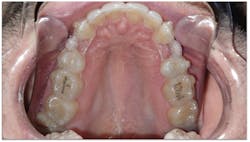

- He measured 28 mm, which is very narrow considering that uncrowded adults measure 35 mm–39 mm.

- His narrow maxilla had a corresponding vaulted palate, which is clearly visible (figure 3).